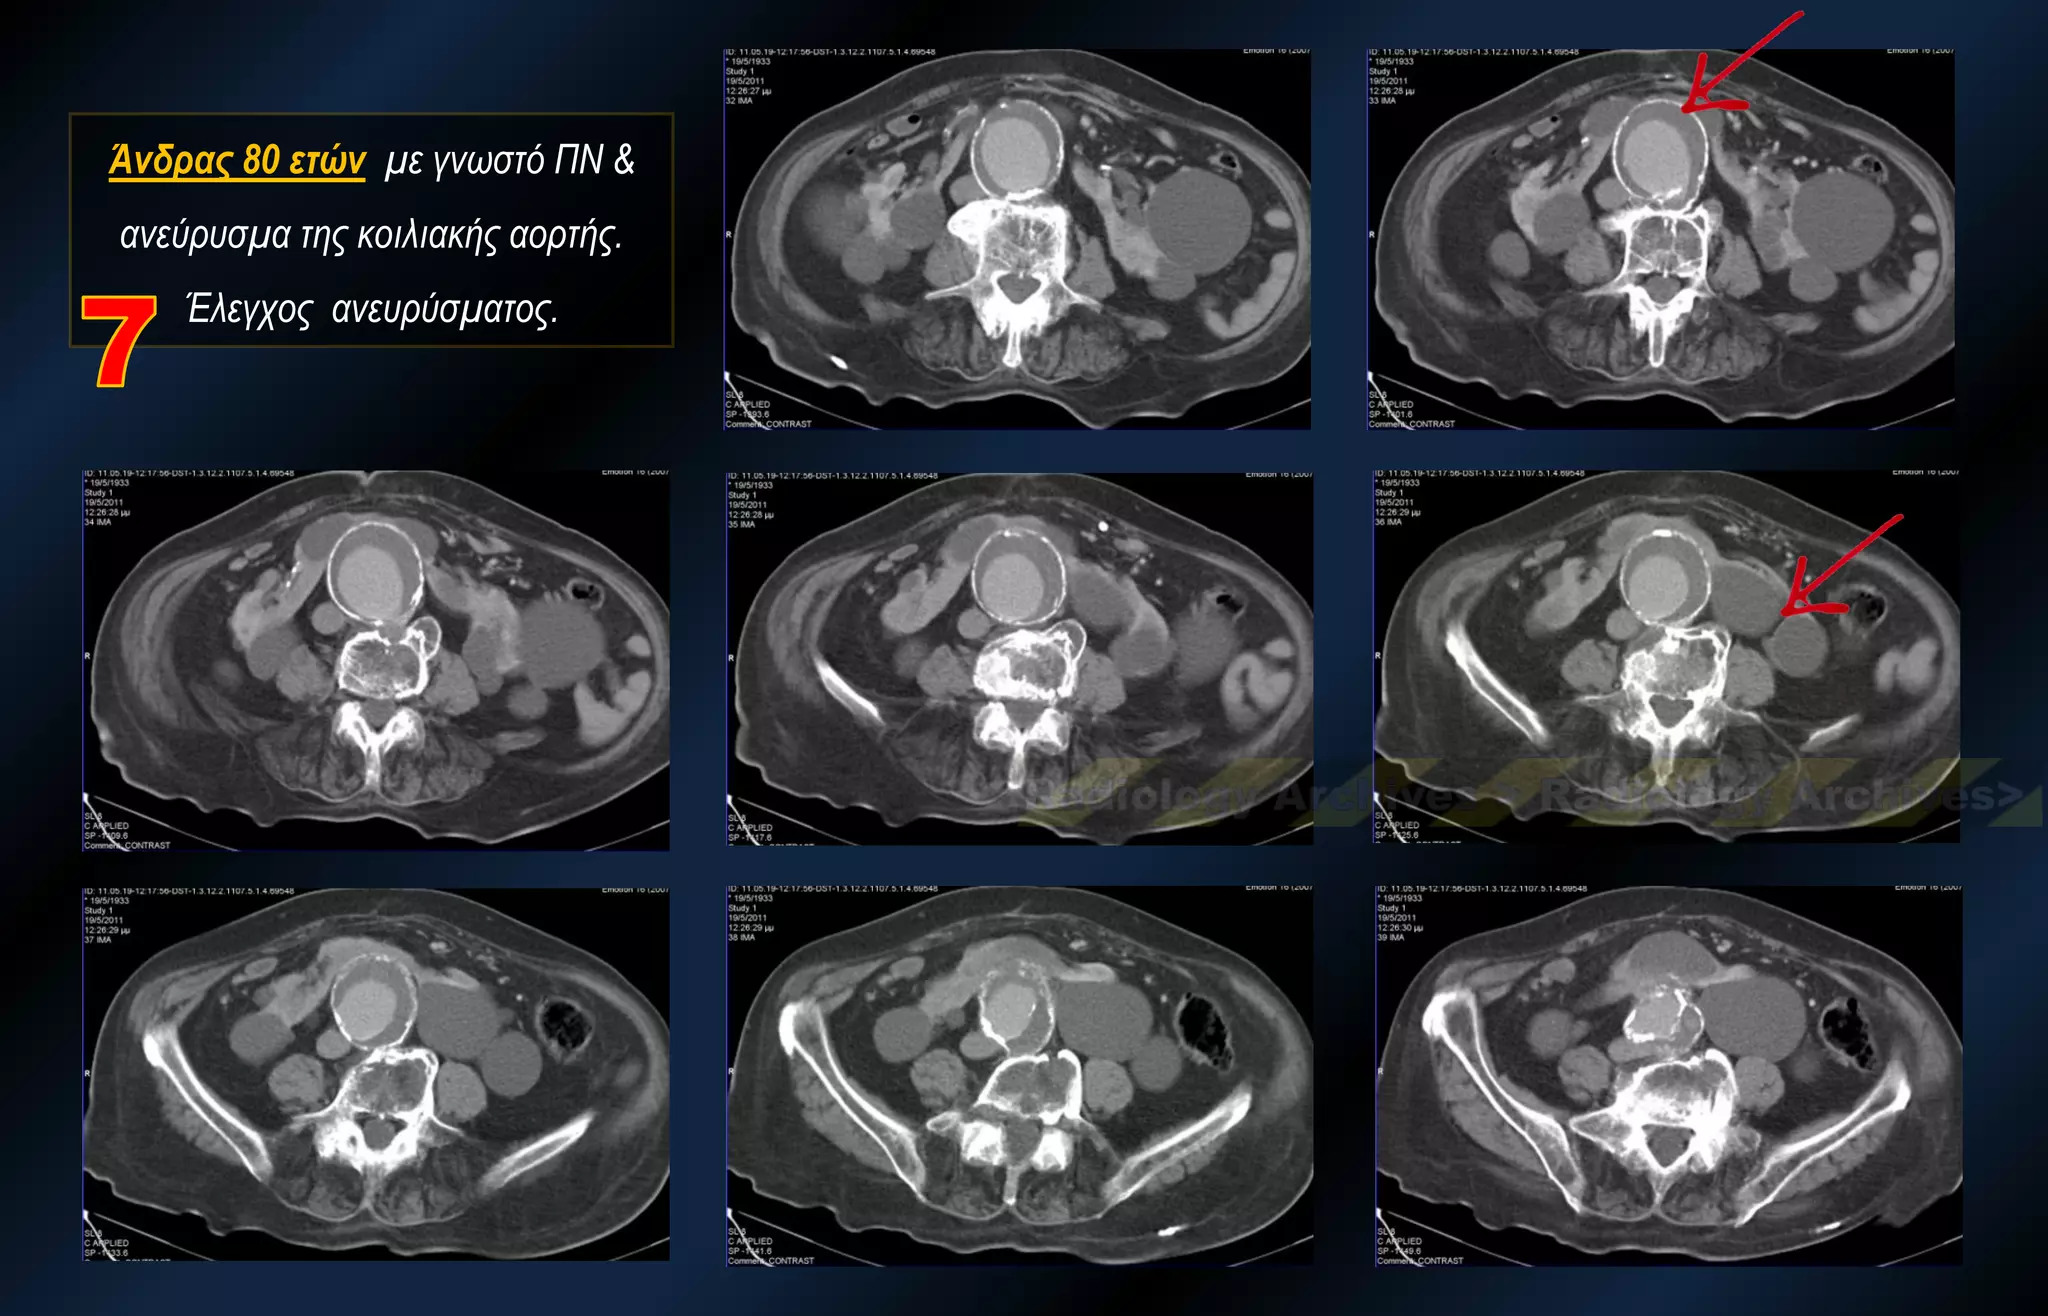

Άνδρας 80 ετών με γνωστό ΠΝ & ανεύρυσμα της κοιλιακής αορτής. Έλεγχος ανευρύσματος.

Άνδρας 80 ετώνμε γνωστό ΠΝ & ανεύρυσμα της κοιλιακής αορτής. Έλεγχος ανευρύσματος.